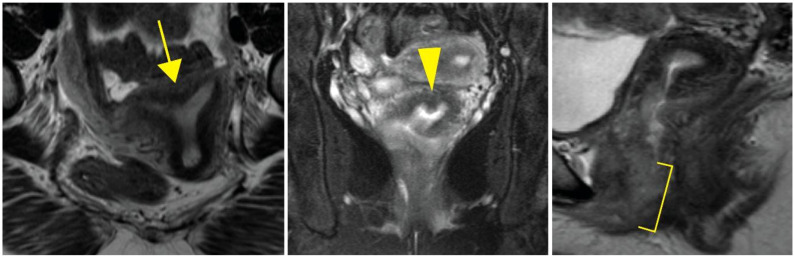

Case: A 38-year-old 46,XX female patient of self-reported Cambodian ancestry was evaluated due to her history of atypical uterovaginal morphology. She had a history of hypertension and nephrotic range proteinuria that was diagnosed early in adulthood. A kidney biopsy at that time revealed FSGS. Following worsening renal function and subsequent end-stage renal disease (ESRD), she underwent a kidney transplant at 33 years of age. After kidney transplant, she presented with hematocolpos and was found to have distal vaginal atresia and an arcuate uterus. She underwent vaginoplasty and then had regular menses. She was noted to have persistently elevated follicle stimulating hormone levels, consistent with primary ovarian insufficiency, but with normal anti-Müllerian hormone levels. Assessment of her family history was suggestive of other individuals in her family with similar renal disease and uterine differences. Genetic analysis identified a WT1 variant (c.1338A>C; p. =) of uncertain significance that is also present in her similarly affected mother. To help clarify the potential impact of this variant, we completed a mini-gene assay to detect in vitro splicing changes in the presence of the WT1 variant sequence uncovered in this individual. This demonstrated resultant aberrant splicing that further supports the pathogenicity of the uncovered variant for this individual.